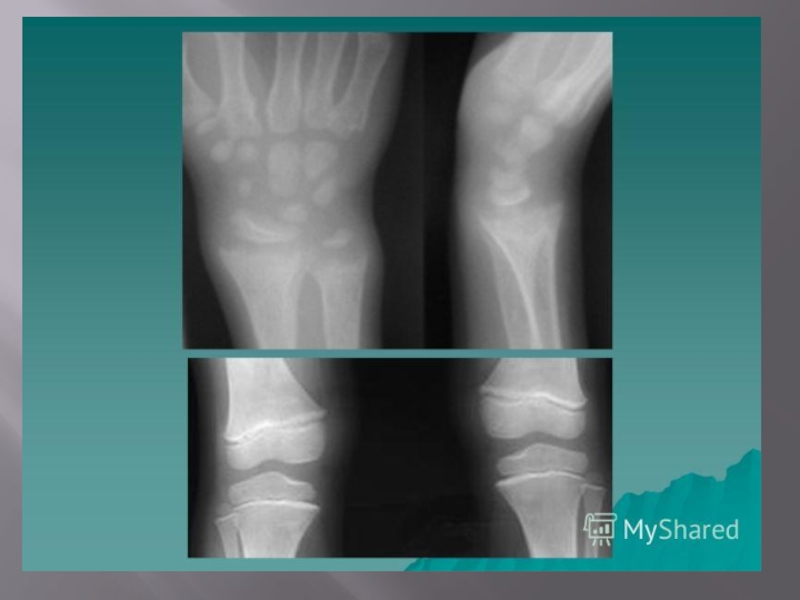

фосфора; снижение концентрации фосфора; повышение активности щелочной фосфатазы; повышение активности щелочной фосфатазы; содержание кальция – N или гипокальциемия; содержание кальция – N или гипокальциемия; снижение содержания лимонной кислоты (гипоцитремия). снижение содержания лимонной кислоты (гипоцитремия). 3. Рентгенограмма костей скелета – остеопороз.

Слайд 29.

III степень

1. Деформация костей черепа, грудной клетки, позвоночника + разнообразные

изменения трубчатых костей: a) верхние конечности: искривление плечевой кости и костей предплечья;

искривление плечевой кости и костей предплечья;

Деформация в области суставов: «браслеты» (утолщение в области лучезапястных суставов), «нити жемчуга» (утолщение в области диафизов фаланг пальцев).

б) нижние конечности: искривление бедер вперед и кнаружи; искривление бедер вперед и кнаружи; разнообразные искривления нижних конечностей (О- или Х- образные деформации,); деформации в области суставов. деформации в области суставов.

Подострое течение Преобладание гиперплазии остеоидной ткани в зонах роста костей («реберные четки», «браслеты», «бугры» и др.). Чаще встречается во втором полугодии, у детей, получающих недостаточную профилактическую дозу витамина Д

процесса. При рентгенологическом обследовании костей – определяются полоски обызвествления в метафизарных зонах трубчатых костей. Данное течение более характерно для вторичного или наследственных форм рахита